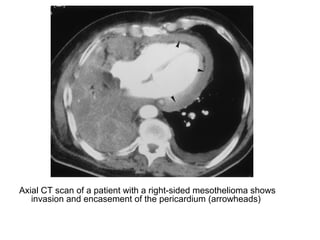

Axial CT scan of a patient with a right-sided mesothelioma shows

invasion and encasement of the pericardium (arrowheads)